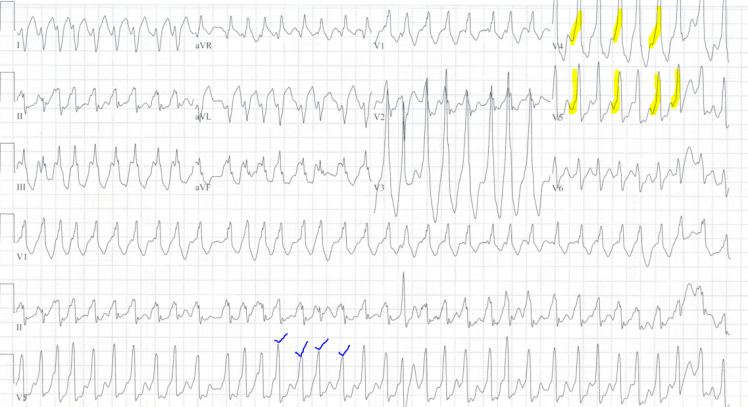

24 y.o. with Near Syncope Gepost op 1 oktober 20171 oktober 2017 door netwerkvsseh #EMconf: 24 y.o. with Near Syncope @emdaily.cooperhealth.org Dit delen: Delen op X (Opent in een nieuw venster) X Share op Facebook (Opent in een nieuw venster) Facebook Delen op LinkedIn (Opent in een nieuw venster) LinkedIn E-mail een link naar een vriend (Opent in een nieuw venster) E-mail Afdrukken (Opent in een nieuw venster) Print Vind-ik-leuk Aan het laden... Gerelateerd